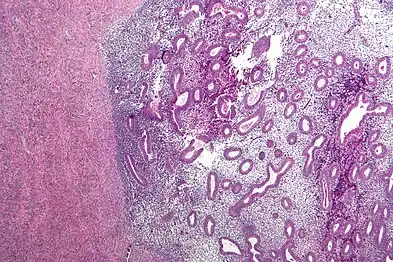

Histopathology

For a histopathological diagnosis, at least two of the following three criteria should be present:[88]

- Endometrial type stroma

- Endometrial epithelium with glands

- Evidence of chronic hemorrhage, mainly hemosiderin deposits

Immunohistochemistry has been found to be useful in diagnosing endometriosis as stromal cells have a peculiar surface antigen, CD10, thus allowing the pathologist go straight to a staining area and hence confirm the presence of stromal cells and sometimes glandular tissue is thus identified that was missed on routine H&E staining.[89]

Micrograph showing endometriosis (right) and ovarian stroma (left). -